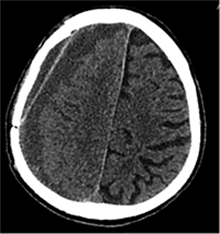

53 m. vyras sumuštas gatvėje ir greitosios medicinos pagalbos atvežtas į Priėmimo skyrių. Pacientui atlikta galvos kompiuterinė tomografija (GKT). Rasta: poūmė, stora, apie 16 mm dydžio subdurinė hematoma (SDH) dešinėje pusėje konveksitaliai ir ūmi nedidelė SDH kairėje pusėje frontoparietaliai. Vidurio struktūrų dislokacija (VSD) į kairę – minimali. Kairėje – kaukolės skliauto linijinis lūžis. Nustatyta nosies kaulų, nosies pertvaros, dešiniojo viršutinio žandikaulio kaktinės ataugos ir kūno, sinuso sienelių lūžių, dešinės akiduobės medialinio krašto lūžių ir dešiniojo skruostinio lanko lūžių (1 pav.). 2020 m. liepos mėn. pacientas skubos tvarka operuotas: atlikta dešinė kraniotomija, pašalinta hematoma. Atlikus kontrolinę GKT, buvo matyti, kad pašalinta didžioji hematomos dalis (2 pav.). Pacientas konsultuotas veido ir žandikaulio chirurgo, skubus chirurginis gydymas neindikuotas. Praėjus 3 savaitėms, pacientas, esant gerai funkcinei ir neurologinei būklei, tolesnio gydymo perkeltas į slaugos ligoninę, vėliau išleistas gydytis ambulatoriškai.

2 pav. Po pirmosios operacijos (didžioji hematomos dalis pašalinta, VSD be dislokacijos)